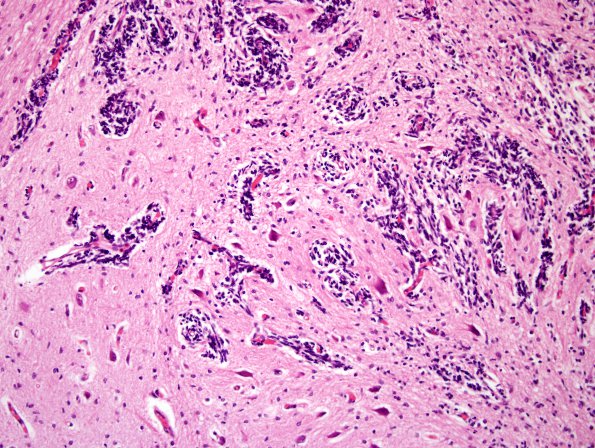

10A5 Cerebellum, Complex malformation (Case 10) 6

Wispy collections of immature granule cells (H&E)